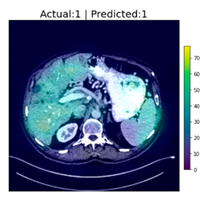

| Image Number | Overlaid Image | Deep Lesion Label | CNN Result | Clinical Radiologist’s Diagnosis | Grad-CAM Helpfulness |

|---|---|---|---|---|---|

| 1 | ![]() | Has Tumor | Has Tumor | Has Tumor | Some |

| 2 | ![]() | Has Tumor | Has Tumor | Has Tumor | Yes |

| 3 | ![]() | Has Tumor | Has Tumor | Has Tumor | Yes |

| 4 | ![]() | Has Tumor | Has Tumor | Has Tumor | Yes |

| 5 | ![]() | Has Tumor | Has Tumor | Has Tumor | Yes |

| 6 | ![]() | No Tumor | Has Tumor | Has Tumor | Yes |

| 7 | ![]() | Has Tumor | Has Tumor | Has Tumor | Yes |

| 8 | ![]() | Has Tumor | Has Tumor | Has Tumor | Yes |

| 9 | ![]() | Has Tumor | Has Tumor | Has Tumor | Some |

| 10 | ![]() | Has Tumor | Has Tumor | Has Tumor | Yes |

| 11 | ![]() | Has Tumor | Has Tumor | No Tumor (Cyst) | Some |

| 12 | ![]() | Has Tumor | Has Tumor | Has Tumor | Yes |

| 13 | ![]() | Has Tumor | Has Tumor | No Tumor | Yes |

| 14 | ![]() | Has Tumor | Has Tumor | No Tumor (Inflammation of the Biliary Tract) | Some |

| 15 | ![]() | No Tumor | Has Tumor | No Tumor (Cyst) | Some |

| 16 | ![]() | Has Tumor | Has Tumor | Has Tumor | Yes |